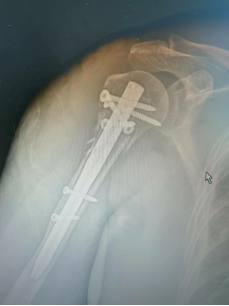

8.肱骨近端骨折闭合复位髓内钉固定